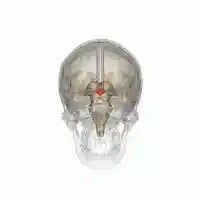

Location of the human hypothalamus | |

Location of the hypothalamus (blue) in relation to the pituitary and to the rest of the brain | |

The hypothalamus (from Ancient Greek ὑπό, "under", and θάλαμος, "chamber") is a portion of the brain that contains a number of small nuclei with a variety of functions. One of the most important functions of the hypothalamus is to link the nervous system to the endocrine system via the pituitary gland. The hypothalamus is located below the thalamus and is part of the limbic system.[1] In the terminology of neuroanatomy, it forms the ventral part of the diencephalon. All vertebrate brains contain a hypothalamus. In humans, it is the size of an almond.

Human hypothalamus (shown in red)